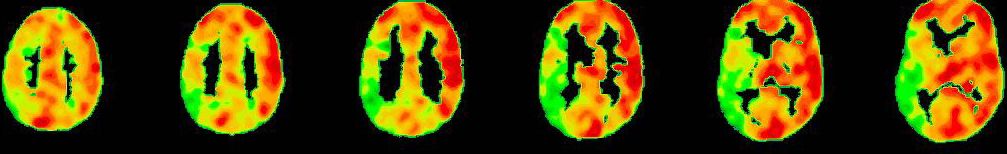

Wissenschaftliche Abbildung

PET/CT mit Darstellung der einseitig reduzierten Reservekapazität/Durchblutung (kalte Farben) im Vergleich zum physiologischen Anstieg der Perfusion auf der Gegenseite (warme Farben).

Die wichtigste Untersuchung zur absoluten Darstellung des Blutflusses im Gehirn im Ruhezustand (baseline) und nach medikamentös stimulierter Gefäßweitstellung ("Diamox/Acetazolamid-Challenge") ist das sogenannte Wasser (H2 15O) PET/CT. Bei dieser Untersuchung wird eine definierte Menge kurzzeitig radioaktives Wasser in das Blutsystem appliziert und somit kann die absolute Blutmenge im Gehirn für jedes Gefäßterritorium bestimmt werden. Dies erfolgt dann sowohl im Ruhezustand und nach Medikamentengabe. Somit kann man die cerebrale Perfusionsreserve absolut darstellen und an Hand dessen Gefäßterritorien mit benötigter Revaskularisation (Anlage eines Bypasses) identifizieren. Auf Grund des benötigten speziellen Nuklearmedizinischen Setups kann diese Untersuchung nur an wenigen Orten in Deutschland durchgeführt werden. Hierfür kooperieren wir mit der Nuklearmedizin der Universität in Freiburg.

PET-CT nach Diamox Gabe

PET-CT nach Diamox Gabe zeigt eine einseitig deutlich reduzierte Perfusionsreserve (grüne Farben) im Vergleich zur Gegenseite mit ausreichendem Anstieg der Durchblutung (warme Farben).